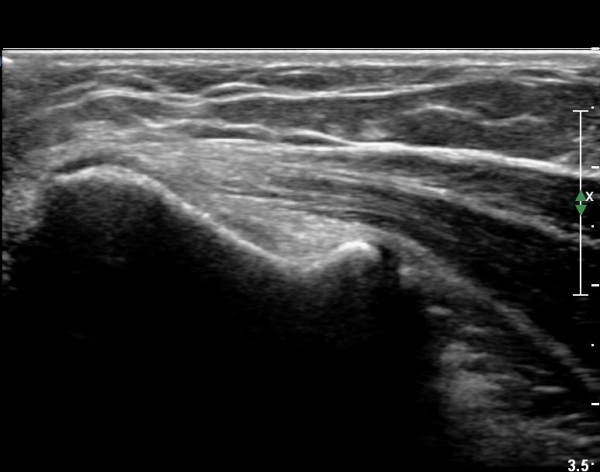

°í¿¡ÄÚ Å½ÃËÀÚ(ÇÏŰ½ºÆ½)·Î °üÂû ½Ã °Ç ºÎÂøºÎ°¡ °í¿¡ÄÚ ¼¶À¯ ¾ç»óÀ¸·Î Á¤»óÀûÀÎ ¼Ò°ßÀ» º¸ÀδÙ(±×¸² 4).

º´º¯ ºÎÀ§·Î ŽÃËÀÚ¸¦ À̵¿ÇÏ±â °Ç ºÎÂøºÎ Àú¿¡ÄÚ º¯¼ºÀÌ ¶Ñ·ÈÇÏ´Ù(±×¸² 5).

ÃÊÀ½ÆÄÀ¯µµÇÏ ÁÖ»çÄ¡·á »çÁøÀ¸·Î ¹Ù´ÃÀÌ º´º¯ ºÎÀ§¿¡ Á¤È®È÷ À§Çϰí ÀÖ´Â °ÍÀÌ º¸ÀδÙ(»çÁø 6).

Áֻ縦 ½ÃÇàÇÏ´Ï ÁÖ»ç¾×ÀÌ ¸¶Ä¡ ³¶Á¾¿¡ ÁÖ»çÇÏ´Â °Íó·³ ÁÖ»çµÇ¾î Àú¿¡ÄÚ º´º¯ ºÎÀ§°¡

ÆÄ¿­µÈ °ÍÀÓÀÌ È®ÀεȴÙ(÷ºÎ µ¿¿µ»ó).